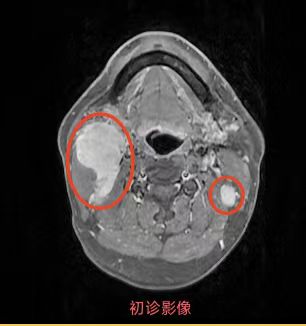

同步放化療(鼻咽癌伴頸部淋巴結(jié)轉(zhuǎn)移)